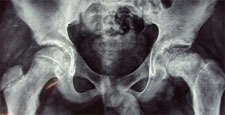

Slipped Capital Femroal Epiphysis (SCFE)

SCFE is a common hip pathology seen more frequently in boys than girls during the adolescent growth spurt. There is a mechanical weakening between the met- aphyses of the femoral neck and head causing the epiphysis to slip posteriorly.

It is more common in children with endocrine disorders, with metabolic bone disease and renal disorders. Children with bilateral slips must be evaluated for thyroid and, growth hormone deficiency and renal causes SCFE may vary from mild (early) slip to moderate and complete slip depending on the extent of displacement of epiphysis. SCFE can also be classified as Stable and Unstable slips depending on the ability of the child to bear weight on the affected leg.

Any acute, and unstable SCFE requires emergent treatment. Stable slips also need to pinned on an elective basis. Untreated or unreduced SCFE can lead to Avascular Necrosis of the epiphysis, chondrolysis and Femoral-Acetabular impingment leading to early hip arthritis. Severe Slip may required open reduction using the Anterior or Watson-Jones Approach or the Safe-Surgical Hip (GANZ) Dislocation approach.